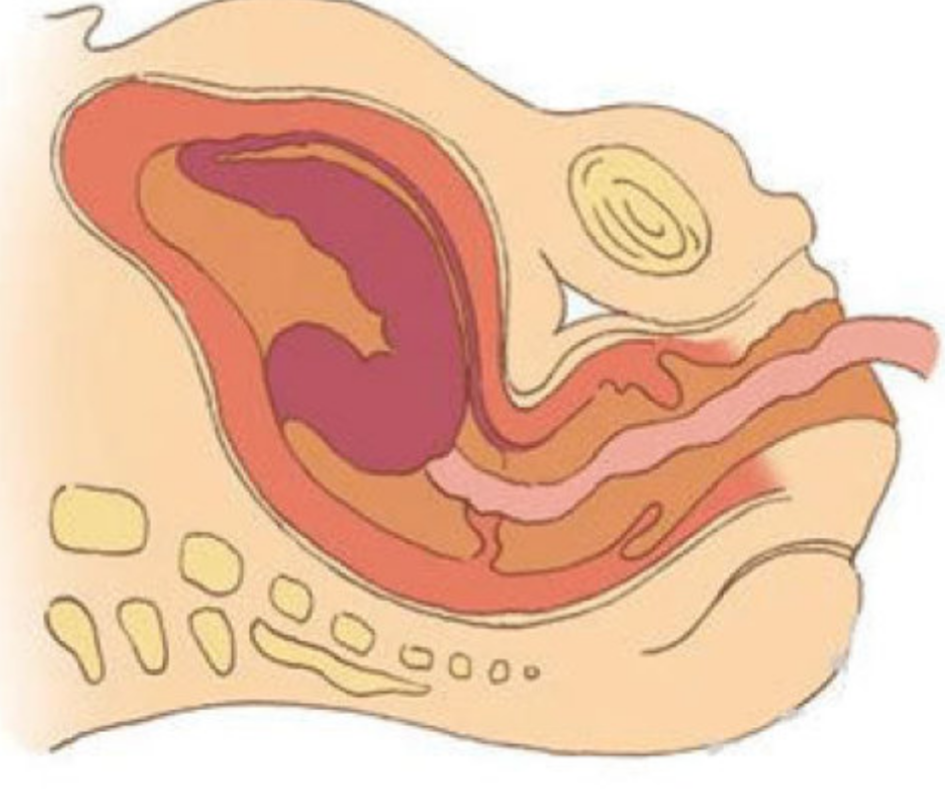

人工陰道漫畫的

治療中人工陰道漫畫

人工陰道漫畫

治療中人工陰道

治療中人工陰道漫畫

治療中人工陰道的

正在治療的人工陰道

治療中的人工陰道的

治療中的人工陰道

正常人工陰道的

正常人工陰道

幼兒人工陰道

正常的人工陰道的

正常的人工陰道

正常女性人工陰道

人工陰道治療中的

人工陰道作用

人工陰道治療

人工陰道治療前期

人工陰道治療前後